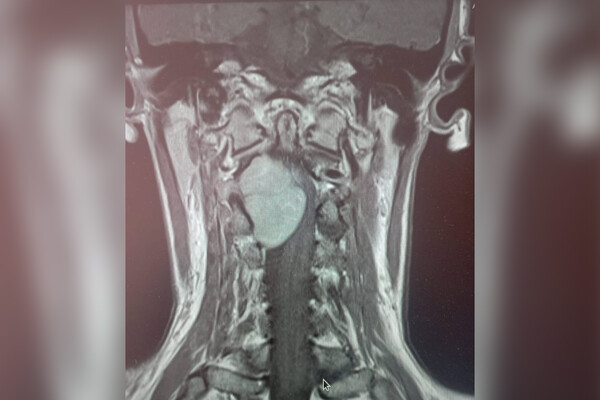

Врачи больницы скорой помощи Липецка прооперировали 35-летнюю женщину с огромной опухолью в шейном отделе позвоночника. Об этом региональный министр здравоохранения Анна Маркова сообщила в своем Telegram-канале.

Пациентка обратилась к медикам с жалобами на отнимающиеся руки и ноги. МРТ показало, что проблема кроется в шейном отделе позвоночника, где выросло большое новообразование.

«Шейный отдел — очень опасная локализация. Спинной мозг здесь переходит в головной, кроме того, в шее проходит большая нервно-сосудистая магистраль. Опухоль в этом отделе представляет серьезную угрозу и может привести к парализации», — рассказал нейрохирург больницы Леонид Осолодченко.